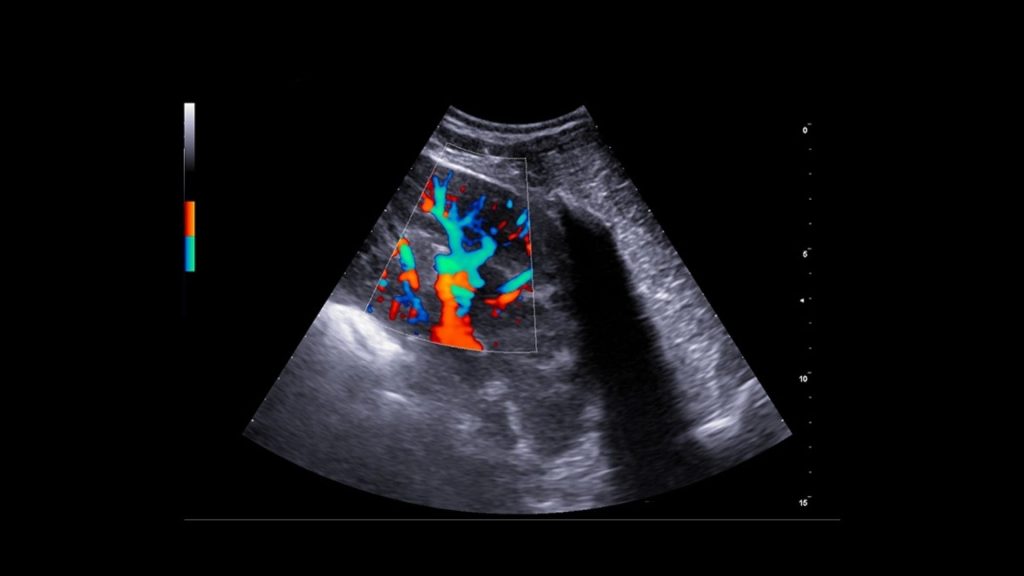

Karaciğer ultrasonografisinde, hepatik parankim (karaciğer dokusu), büyük hepatik ve portal damarlar, bitişiğinde caudal vena cava ve safra kesesi ve bilier sistem incelenir. Radyografiden farklı olarak ultrasonografi, hedef yapıların çeşitli düzlemlerden görüntülenmesine olanak sağlar. Karaciğerin ultrasonografik muayenesi sırasında hekimin tercihine göre hasta sağ yan, sol yan veya sırt üstü pozisyonlarında yatabilir. Daha iyi görüntü alınabilmesi için karın bölgesi göğüs bölgesine kadar tıraşlanıp temizlenmelidir. Görüntü kalitesini hastanın vücut yapısı, karaciğerin boyutu ve gastrointestinal içerik etkileyebilir. Mide içeriğindeki gaz iyi bir karaciğer görüntülemesinin önündeki en önemli engeldir. Bu sebeple hastanın aç olarak muayene getirilmesi tercih edilir. Karaciğer ultrasonografisine ihtiyaç duyulan durumlar, karaciğer hastalıklarıyla ilişkili klinik belirtiler (kusma, ishal, abdomende genişleme, abdomenin elle muayenesinde karaciğer boyutunun arttığının farkedilmesi vs.), laboratuvar analizlerinde biyokimyasal değişiklikler (ALT, ALP, AST, NH3, GGT, BİLİRUBİN, TOTAL PROTEİN, ALBUMIN), ikterus (sarılık), hepatomegali, asites, akut abdomen veya abdominal kitle şüphesi, metastatik kitle şüphesi, hepatik enseflaopati, immun sistem hastalıklarını içermektedir. Hepatik arterleri ve intrahepatik dallarını görüntülemek için Doppler muayenesi gereklidir. Doppler ultrasonografi ile hepatik arter, portal ven ve caudal vena cava incelenebilir. Konjenital veya edinsel Portasistemik Şantla (PSŞ) ilişkili klinik veya laboratuvar belirtileri olan hayvanlarda intrahepatik veya ekstrahepatik anormal damarlar da saptanabilir. Doppler görüntüleme ile aynı zamanda intrahepatik portal hipertansiyonun da tanısı konulabilmektedir.

Veteriner hekimlerimize ve sevimli dostlarımıza merkezimiz bünyesinde vermiş olduğumuz Veteriner USG hizmetimizde Esaote MyLAB X8VET Üst Düzey Renkli Doppler Ultrasonografi Cihazı ile hizmet vermekteyiz. Cihaz ile yapılan sonografik ve doppler çalışmalarında her türlü patolojilerde yüksek çözünürlükte görüntüleme imkanı sağlanmaktadır. İçerdiği yazılımlar ile tanıyı detaylandırarak teşhise götüren götürmeye yardımcı olmaktadır. Çoklu modalite aracı ile, hızlı bir tanıya ulaşmak için gerçek zamanlı ultrason görüntülemeyi çok çeşitli ikinci görüntüleme modaliteleriyle (MRI, CT, 3D Görüntüleme, Doppler) birleştirmek mümkündür.